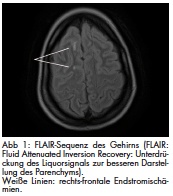

Die Defektdeckung im Bereich der vorderen Lamelle kann frei oder gestielt erfolgen. Freie Transplantate können vom ipsi- und/oder kontralateralen Oberlid – hier im Sinne einer Hautgewinnung durch eine Oberlidblepharoplastik -, von retro- oder präaurikulär oder der Oberarminnenseite entnommen werden. Hinsichtlich etwaiger Textur und Farbunterschiede der Transplantate hat sich die Oberlidhaut am geeignetsten erwiesen (Abbildung 1). Bei der Transplantation ist darauf zu achten, dass das Transplantat ausreichend ausgedünnt und spannungsfrei eingenäht wird. Insbesondere eine Spannung in vertikaler Richtung führt nicht selten zu einer Unterlidfehlstellung, im Extremfall zu einem Unterlidektropium [10]. Eine gewisse Schrumpfungsneigung ist ebenfalls zu berücksichtigen. Gestielte Transplantate sind typischerweise Semizirkularlappen von lateral (z. B. nach Tenzel), oder lokale Verschiebelappenplastiken (Z-Plastik, V-Y-Plastik, horizontale Verschiebelappenplastiken, o. ä.). Insbesondere bei Hautdefekten über die gesamte Unterlidbreite ist der temporal gestielte Transpositionslappen aus dem Oberlid geeignet, um diesen Defekt zu decken und gleichzeitig einen vorteilhaften Zug entlang des natürlichen Verlaufes des M. orbicularis oculi zu erreichen.